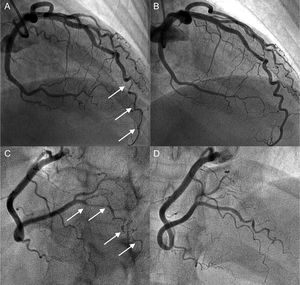

The therapeutic management of patients with SCAD is summarized in Table 3. Percutaneous coronary intervention was performed in half of the patients; 64% (n = 23) of these patients received a drug-eluting stent. Percutaneous coronary intervention was used primarily for patients diagnosed more than 10 years earlier, and conservative medical management was more frequent in more recently diagnosed patients (27% were conservatively managed before 2011 vs 61% after; P = .008). Only 1 patient who had a concomitant aortic dissection required coronary artery bypass surgery. Notably, a more conservative medical treatment strategy was chosen (79% [n = 15] vs 41% [n = 22]; P = .007) in the SCAD group with hypothyroidism (with a more distal and diffuse involvement and somewhat smaller and more tortuous vessels). Illustrative examples from this series are shown in Figure 1 and Figure 2.

Coronary angiogram in a hypothyroid patient with multiple spontaneous coronary artery dissections. A and B: angiogram of the anterior descending artery with type 2 dissection (intramural hematoma) with involvement of a distal corkscrew segment (arrows) and its resolution during follow-up. C and D: angiogram of the right posterolateral branch with type 2 dissection (arrows) and its resolution during follow-up.